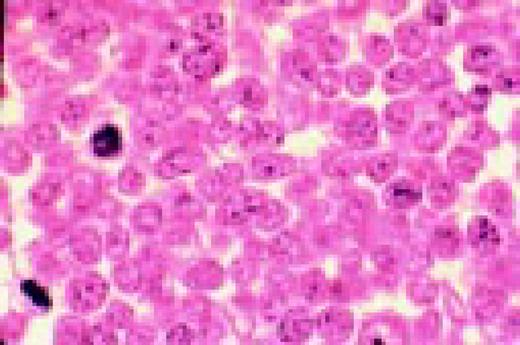

Slide L40

Multiple myeloma, bone marrow aspirate. The marrow has been completely replaced by abnormal plasma cells. A binucleate plasma cell is seen in the center of the field.FIG40